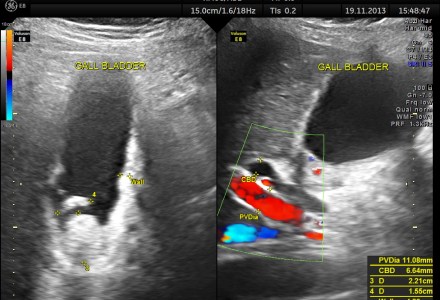

GALL BLADDER VARICES